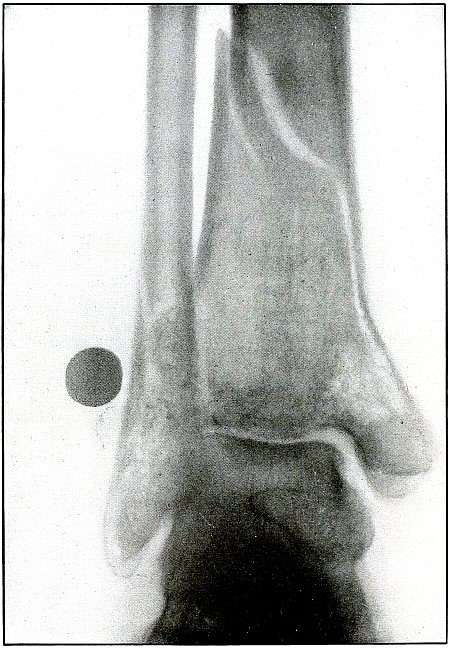

Plate 59.

_

[Pg 129]

Rifle—Plate 59.

LOWER EXTREMITY.

Gunshot Wound of the Left Knee-Joint,

with Lodgment of the Missile in the Joint.

The course of the bullet was transverse, entering the capsule posterior to the patella without injury to the bone.

As its shadow projection is almost circular, the bullet must be standing almost on its end pointing toward the plate with its long axis almost parallel to the line of projection.

As the fibular side of the leg lay next to the plate and as the only slightly enlarged shadow of the bullet indicates it to be near the plate, its position is in the joint near the fibular side.

As the bullet is undeformed and its penetrating power very slight, its velocity was that of extreme range.

The emergency treatment, is, of course, a simple antiseptic dressing with the leg held in the most comfortable position by muscular action.

The subsequent treatment is removal of the bullet when proper surgical conditions obtain. [Pg 130]